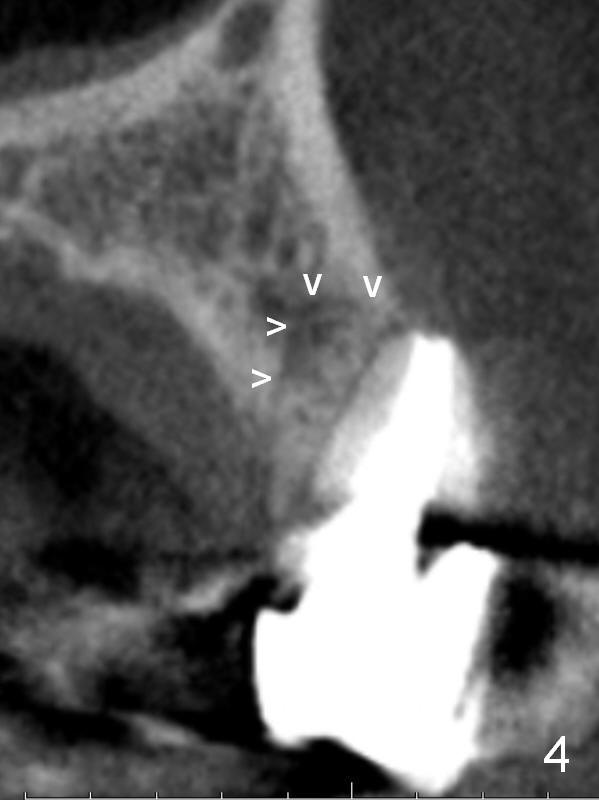

A 4.5x14 mm bone-level or 4.5x17 mm tissue-level implant appears to be appropriate for the site according to the PA (Fig.6,7).  CBCT shows that there is enough bone to place a 4.5x20 mm tissue-level implant (Fig.8).  This is more appropriate, considering the large radiolucency (Fig.5), the age of the patient (possibly osteoporosis), and the maxilla (bone softer than that of the mandible).  The implant will be supported by approximately 8 mm solid bone apically (Fig.8).

After extraction, the bottom of the socket must be oblique (Fig.9 arrowheads). As usual, osteotomy is initially at the junction of palatal (Fig.10 P) 1/3 and middle 1/3 perpendicular to the plate.  Once the drill gets engaged, the trajectory is to be changed (Fig.11 curved arrow) so that the apical end of the osteotomy (red line) is as close to the buccal plate (B) as possible.  The purpose is to keep the palatal end of the osteotomy as palatal as possible.  In spite of the effort, an angled abutment is expected, as large as 20 degree (Fig.8 purple angle).

After preparation of the implant and abutment and fabrication of an immediate provisional, a cone-shaped Osteo-tape (Fig.8 orange outline) is inserted against the buccal socket wall (most likely completely soft tissue), followed by bone graft (red circles, to the level of the palatal crest (>)).